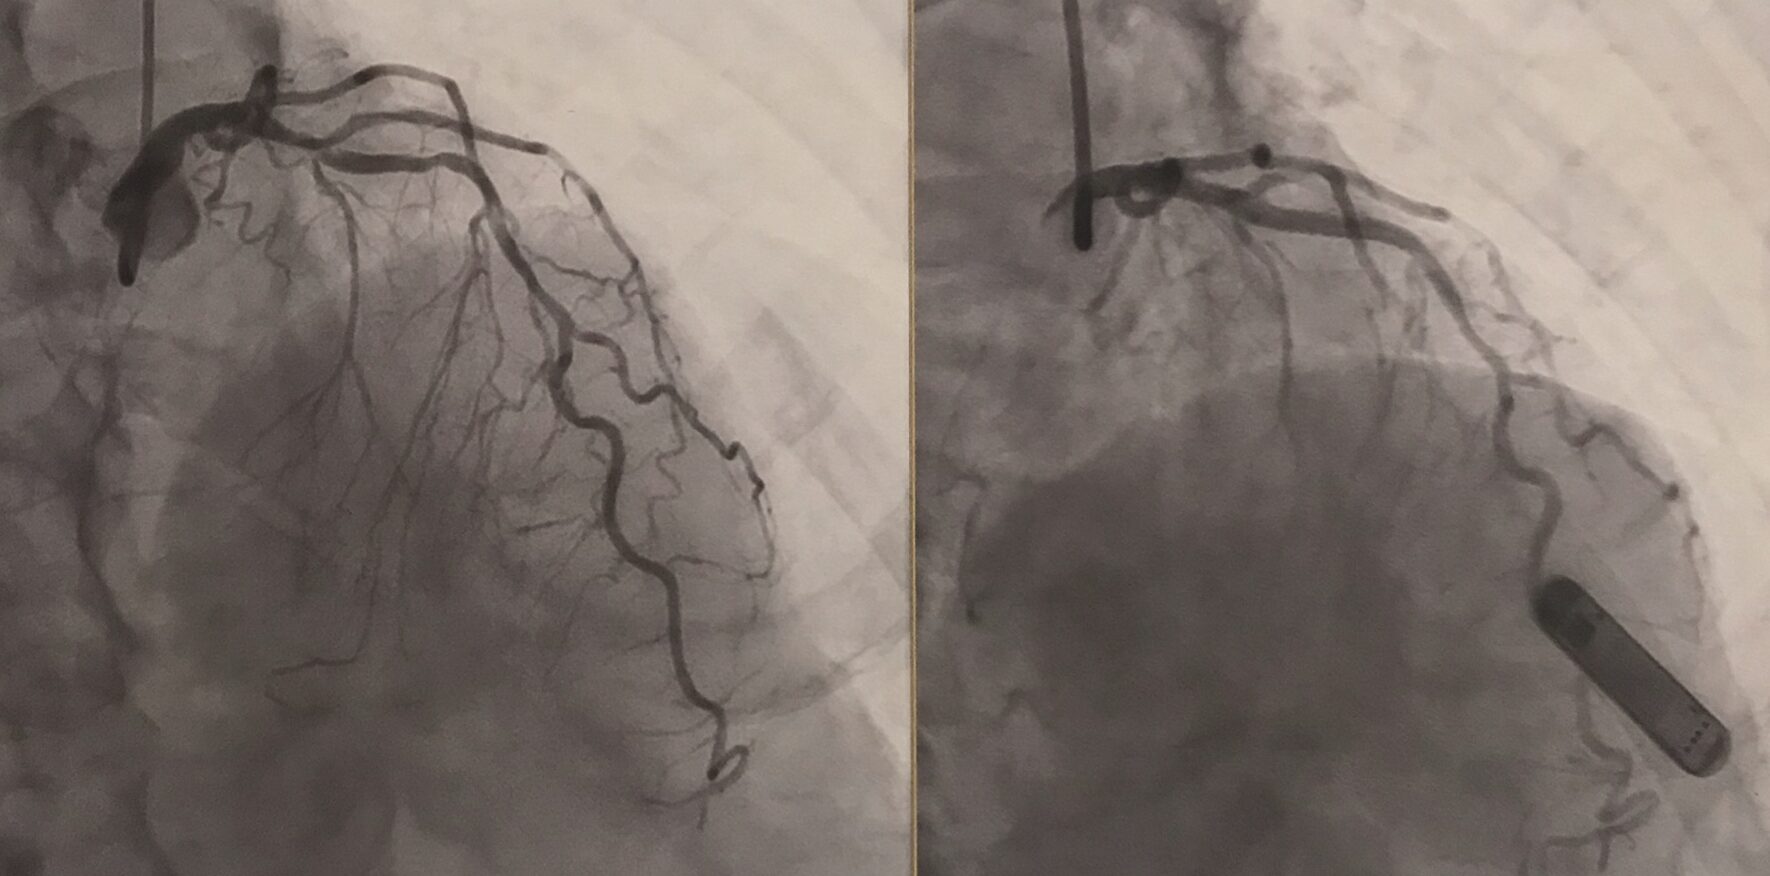

なんやかんやで2回目の手術の事も記事にしないでただ真面目に生きています。

今回はこのくらいで終わりますが、次の記事で2回目の手術の事を報告しようかと思います。

既に2回目の手術が成功した事は言うまでもないと思いますが、詳細を次回に報告しようと思っています。